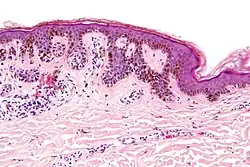

Ein Dysplastischer Nävus (auch Dysplastischer melanozytärer Nävus, Clarks Nävus oder Atypischer Nävus) ist eine gutartige (benigne), erworbene, pigmentierte (melanozytische) Neubildung (Neoplasie) der Haut, die wahrscheinlich eine proliferative Phase im Lebenszyklus eines gewöhnlichen erworbenen Muttermals ist und damit eine Variante dieser.[1] Im Aussehen teilen sie sich einige Eigenschaften mit dem Melanom, dem schwarzen Hautkrebs: Asymmetrie, unregelmäßige Ränder, verschiedene Farben innerhalb des Hautflecks und Durchmesser von mehr als fünf Millimeter, was ihre Unterscheidung vom Melanom klinisch und histologisch erschweren kann. In der feingeweblichen Untersuchung (Histologie) zeigen sich architektonische Unordnung, zelluläre Atypien und unterschiedliche Grade an Entzündungen und Fibrosen.[2] Dysplastische Nävi entstehen sporadisch oder im Rahmen einer familiären Häufung. UV-Strahlen und genetische Faktoren spielen in ihrer Entstehung eine entscheidende Rolle.[1]